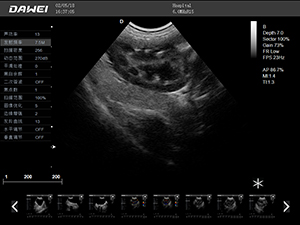

F5-VET彩色多普勒動物超聲診斷儀

F5-VET是一款性能可靠的獸用全數字彩色多普勒超聲診斷系統,基于Windows平臺 配置固態盤快速啟動 穩定可靠,融合了全面豐富的臨床應用,結合優異的人機工程學設計,推動了臨床診斷新趨勢。

·中小動物的肝、膽,脾、腎、膀胱、子宮、妊娠等各組織器官的檢查和病變的診斷